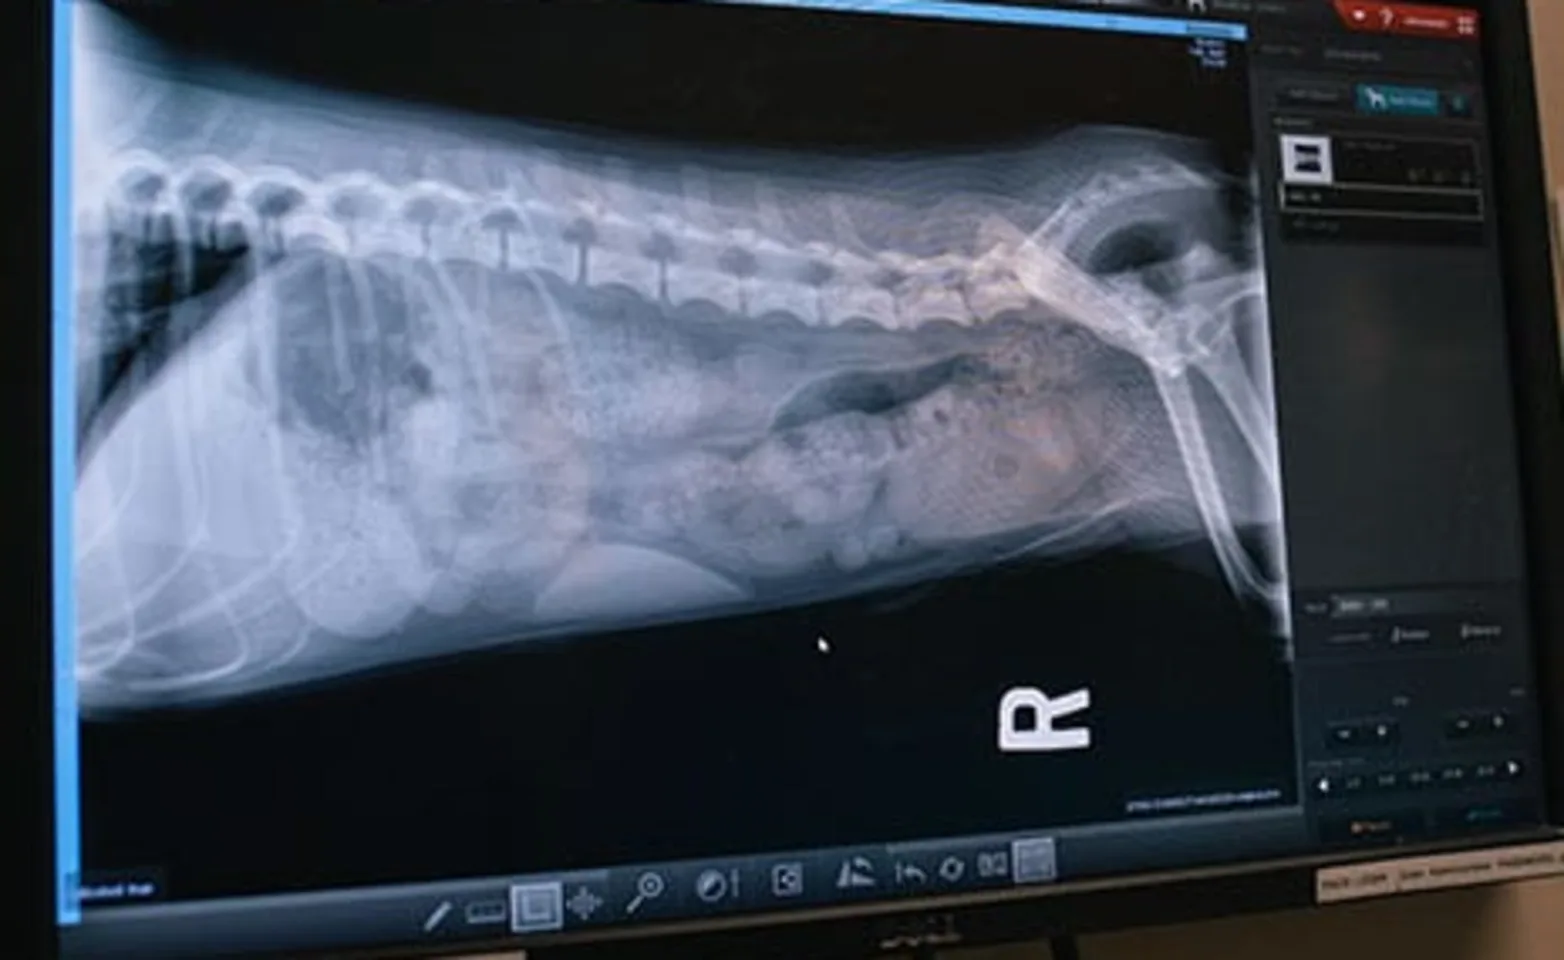

Digital radiography (X-rays): A form of imaging in which digital X-ray sensors are used instead of the traditional photographic film; digital X-rays use less radiation and produce higher-quality images quickly—which means less time on the X-ray table and less stress for your pet

Contrast radiography: The use of X-rays along with a special dye (given intravenously), called a contrast medium, highlights specific areas in the body and helps them to be seen in greater detail on the X-ray image